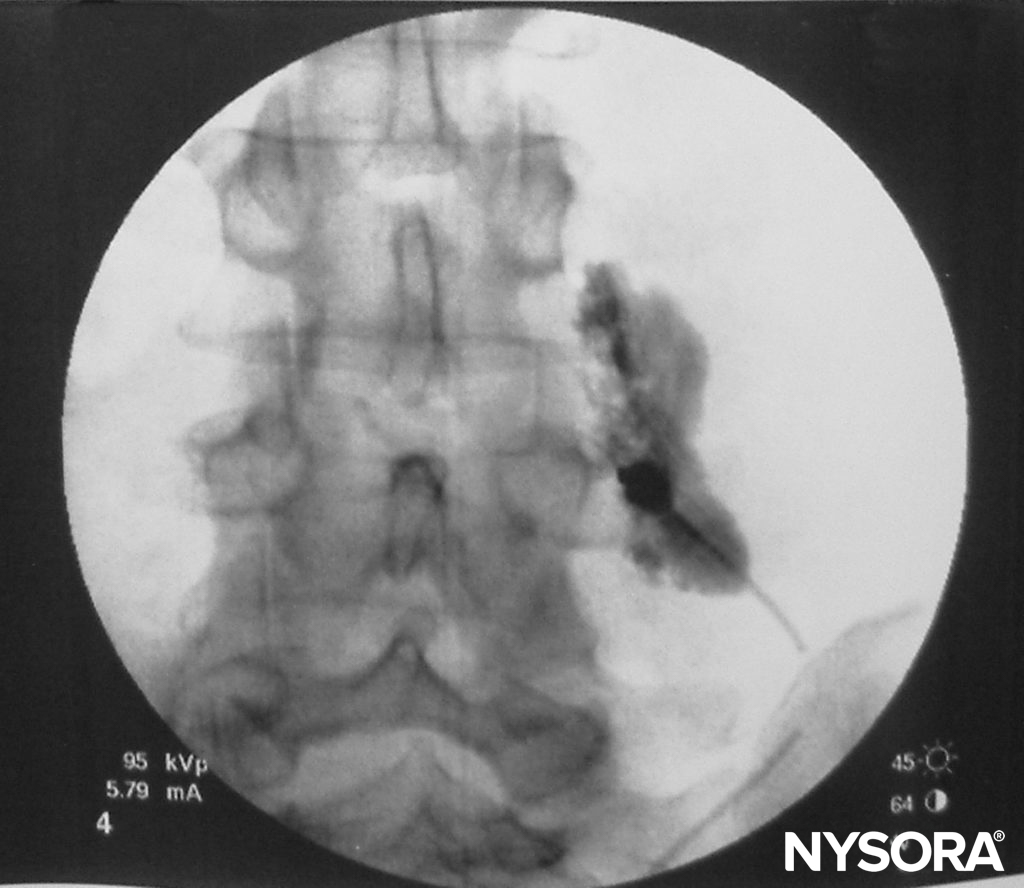

FIGURE 5. Spread of 3 mL of local anesthetic solution after a paravertebral block (lumbar spine).

TPVB produces ipsilateral somatic and sympathetic nerve block (Figure 4) due to a direct effect of the local anesthetic on the somatic and sympathetic nerves in the TPVS, extension into the intercostal space laterally, and the epidural space medially. The overall contribution of epidural spread to the dermatomal distribution of anesthesia following a TPVB is not well defined. However, some degree of ipsilateral spread of local anesthetic toward the epidural space probably occurs in the majority of the patients, resulting in a greater distribution of anesthesia than occurs with paravertebral spread alone. The dermatomal distribution of anesthesia following a single injection of a large volume varies and is often unpredictable, but the injected solutions routinely spread both cephalad and caudad to the site of injection to some extent (Figure 5). Nevertheless, the multiple injection technique, where small volumes (3–4 mL) of local anesthetic are injected at several contiguous thoracic levels, is preferable over single, large-volume injection. This is particularly important when reliable anesthesia over several ipsilateral thoracic dermatomes is desired, such as when TPVB is used for anesthesia during breast surgery. Segmental contralateral anesthesia, adjacent to the site of injection, occurs in approximately 10% of patients after single-injection TPVB and may be due to epidural or prevertebral spread.